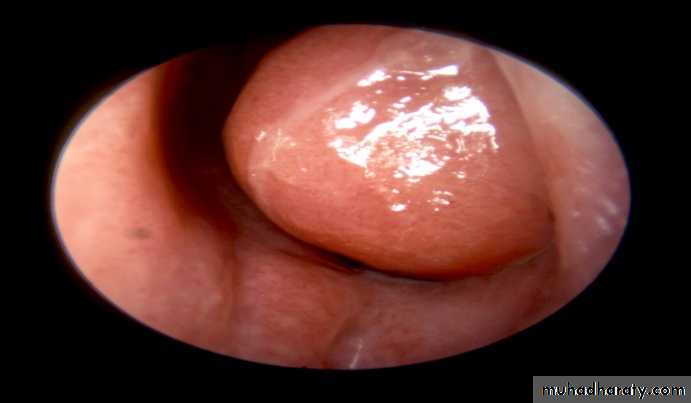

• b)Hypertrophic rhinitis

• Aetiology• The condition represent an advanced stage of simple chronic rhinitis , in which permanent hypertrophic changes have followed . the causes are similar , but it is frequently seen also in patient who have used topical decongestant in large quantities and /or for long periods ( rhinitis medicamentosa )

• Pathology

• .permanent hypertrophic changes accompany the inflammatory oedema and cellular infiltration in all the constituent parts of the mucosa i.e. stroma , glands , blood vessels , and lymphatic tissue . the epithelium loses clilia and shows a tendency to squamous metaplasia . the mucosa becomes thick and nodular , especially at the extremities and free border of the the occupy the posterior choana . fibrosis can cause venous and lymphatic obstruction . if the resulting passive edema occurs in the situation where the mucosal stroma is loose , polypi form . nasal polyposis , however , usually indicate an allergic or vasomotor origin of the rhinitis , in which the polyposis results from increases capillary permeability• Clinical features

• Similar to those of simple chronic rhinitis but are unremitting in character pitting of the firm mucosa with a probe and shrinkage with cocaine are less marked than in simple chronic rhinitis• Treatment

• As for simple chronic rhinitis , with the addition of limited reduction of the hypertrophied inferior turbinate and removal of any polypi . topical decongestant preparation must be discouraged or discontinued . reduction is achieved by :• . electrocoagualtion : by SMD or linear cauterization by galvanocautery

• .cryosurgical probe

• Surgical trimming of the hypertrophied free border . amputation of an posterior end end may be necessary . avulsion or total removal of the inferior turbinate may be performed , but persistent crusting can result